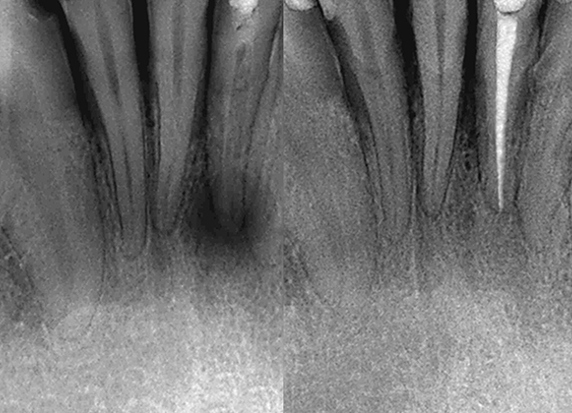

More InfoRoot Canal Therapy

Root Canal treatment can save a tooth from extraction and relieve pain caused by inflammation and infection